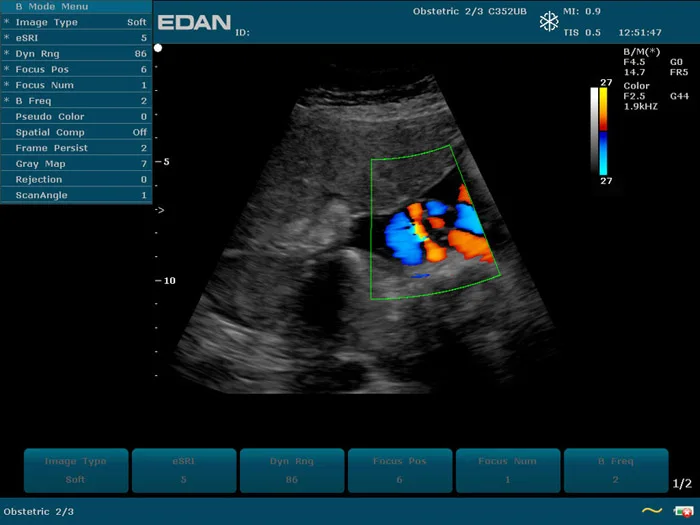

Прибор u2 143 фото